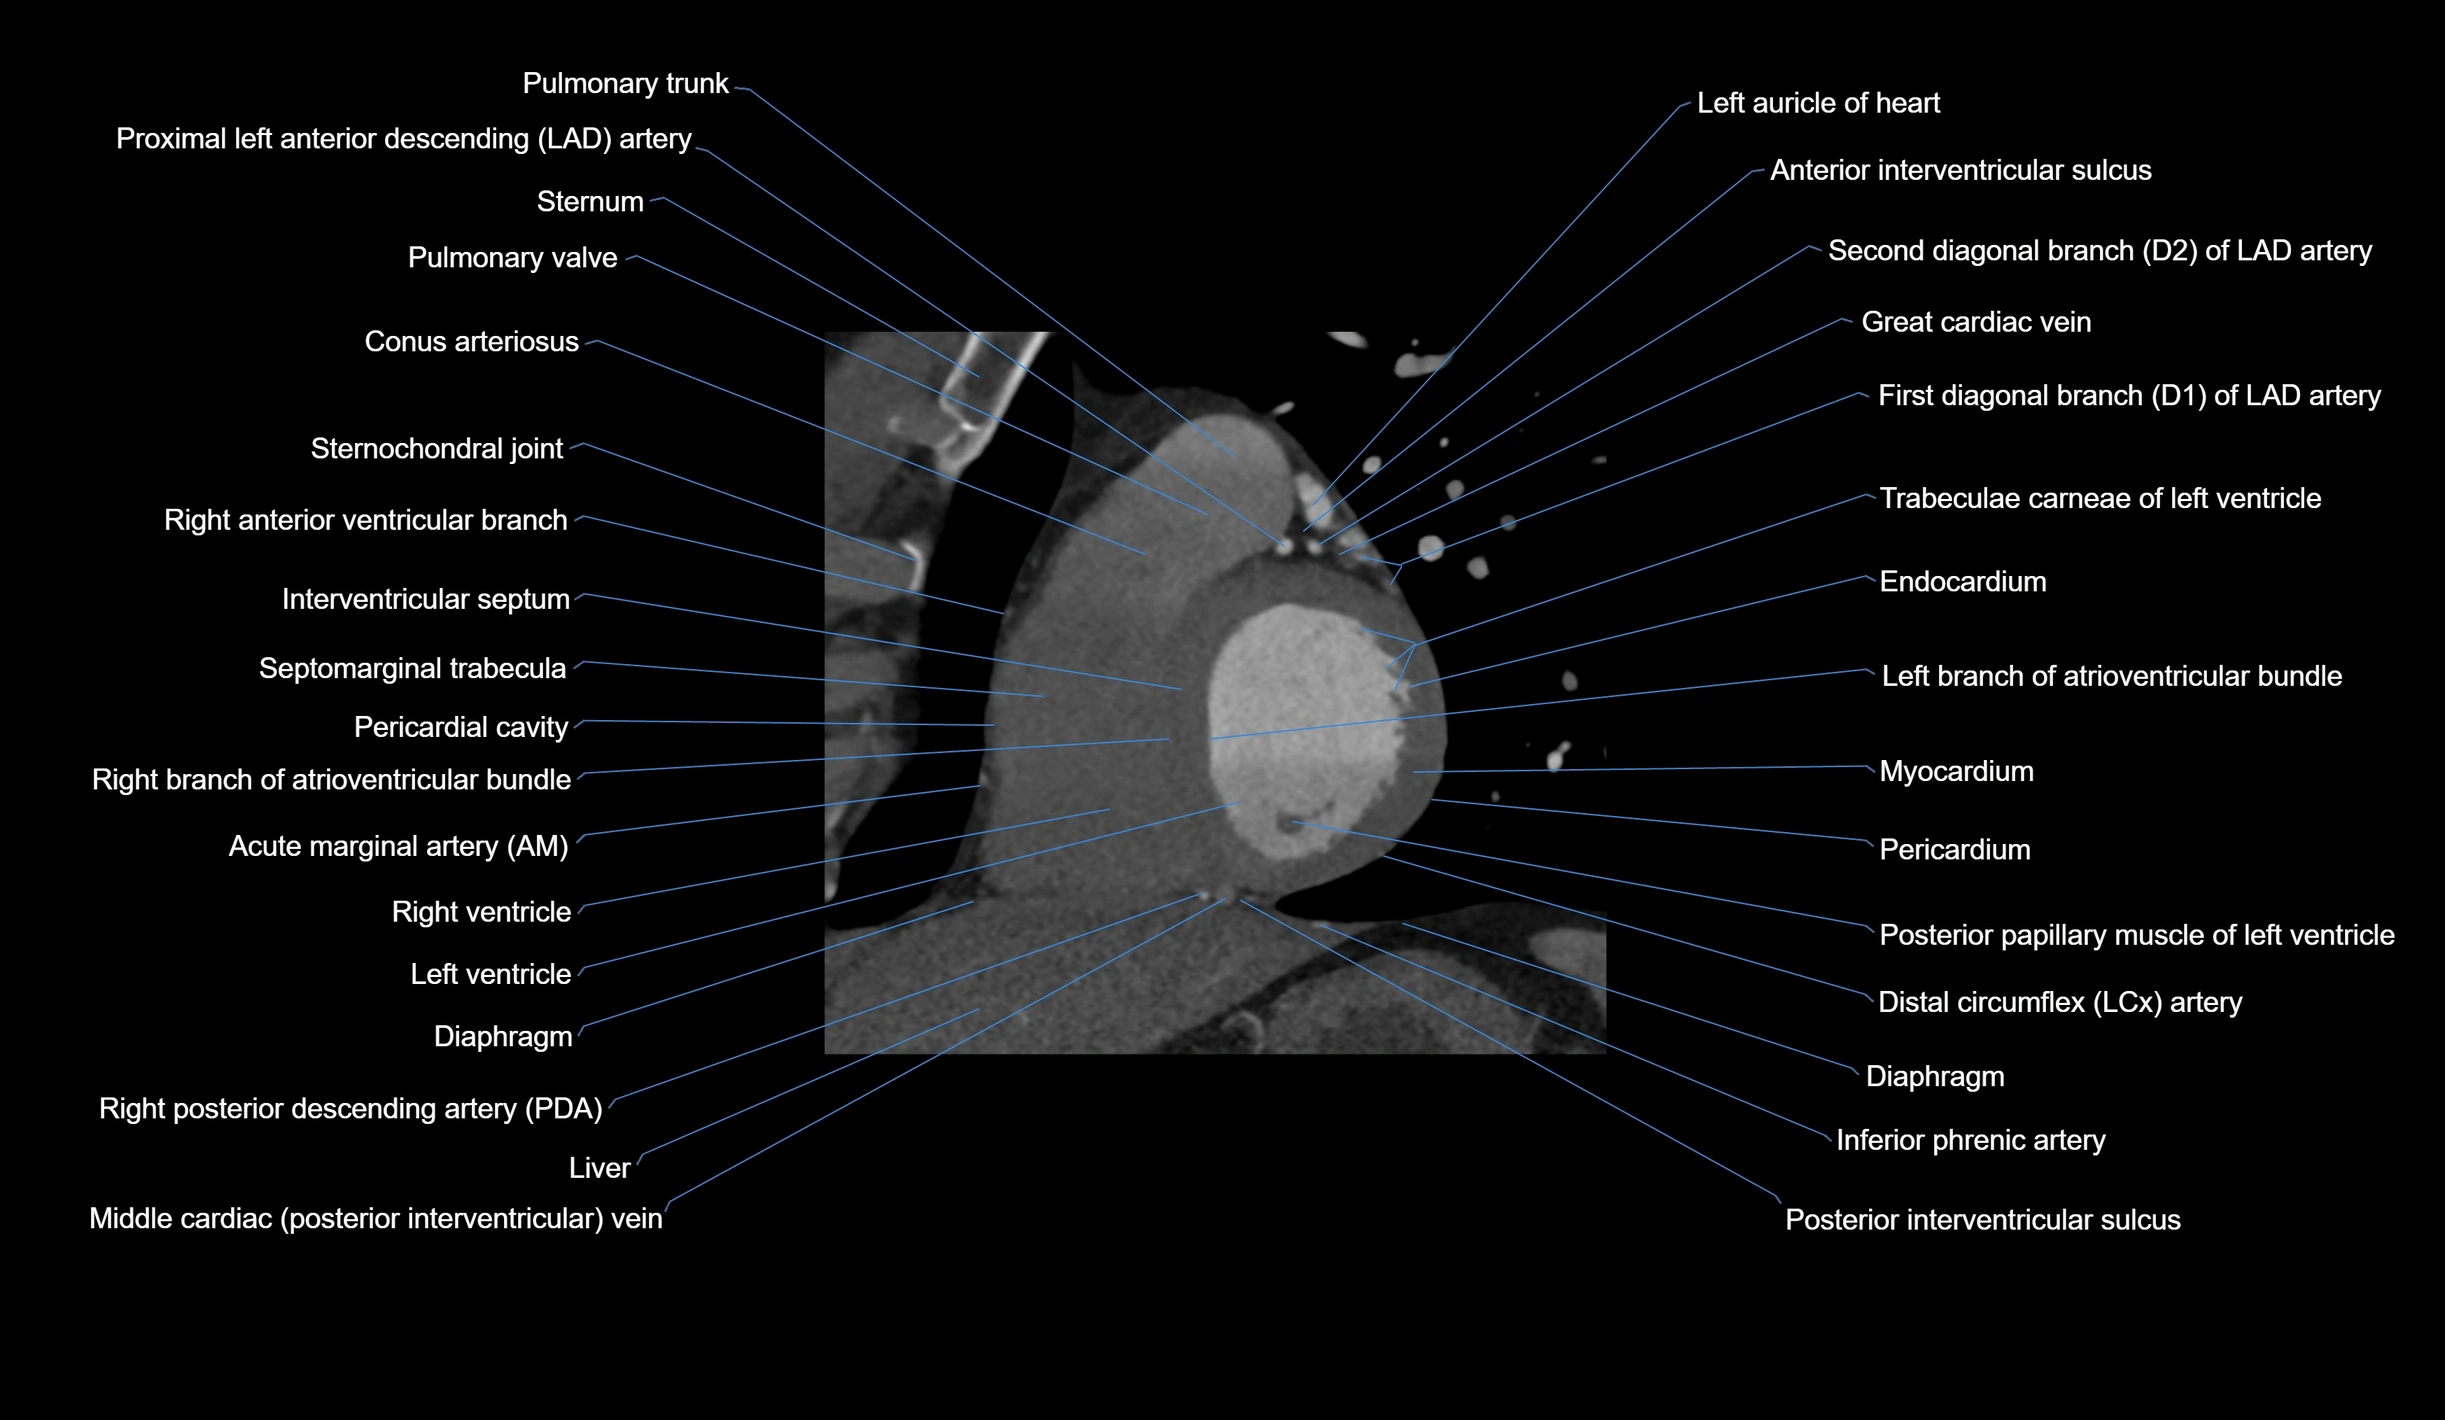

CT Appearance

Non-contrast CT (Calcium Scoring):

-

AM artery visualized for coronary calcium scoring

Calcified plaques appear as hyperdense foci; scored with Agatston method

CT Coronary Angiography (CCTA):

Best non-invasive modality for acute marginal artery visualization

Shows origin, course along the acute margin, and right ventricular branches

Detects stenosis, occlusion, calcified and non-calcified plaques, aneurysm, or anomalous course

Multiplanar reformats and 3D reconstructions help in pre-PCI and surgical planning

Critical for assessing right ventricular infarction risk in RCA disease

MRI image

CT images